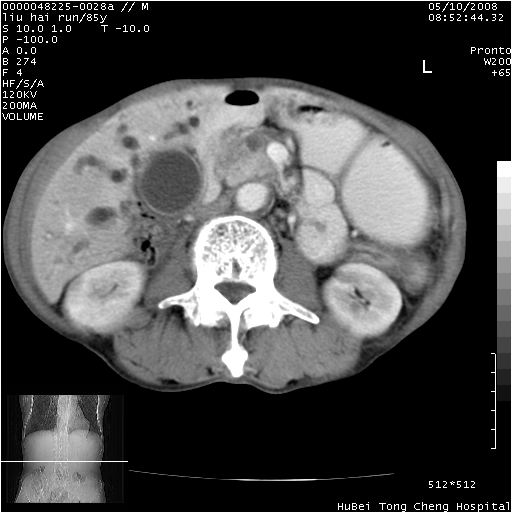

标题: CT13403:M,85Y。胆系低位梗阻。胰头占位?

彩超示胰头实质欠均匀,胰管扩张。

有“双管征”,胆总管胰头段突然中断,考虑为胰头癌。

影像表现:壶腹部扩张胆管呈截断样改变,肝内外胆管重度扩张,胆囊增大,胰管亦明显扩张,呈不规则患珠样,胰体尾部略有萎缩,增强扫描后壶腹部低密度影轻度强化,与钩突分界不清。

ct诊断:胆管癌。鉴别诊断:胰腺癌,胰腺癌为少血供肿瘤,增强后强化不明显,静脉期及延时后与正常胰腺分界清晰。

胆总管下端突然截断,胰腺萎缩,胰管扩张,肝内外胆管扩张,考虑胆总管下端癌可能性大。不除外胰腺钩突占位。

1)胆系低位梗阻(肝内外胆管扩张、胰管扩张、胆囊增大);考虑为:胰头癌可能性大,不排除胆总管下端癌。2)双肾多发囊肿。